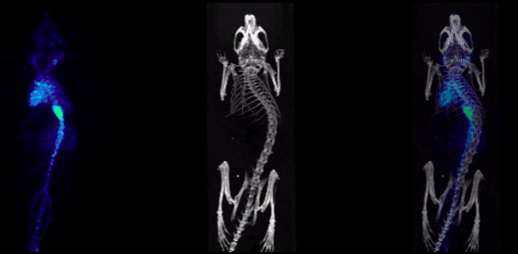

3、和光學成像組合的CT成像

CT圖像可以和小動物活體光學圖像融合,用于結構性成像,輔助定位。

圖14. CT和光學融合圖.png